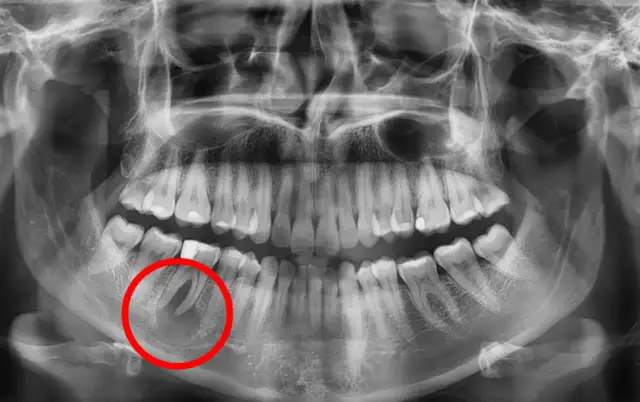

Czy masz torbiel zęba? Objawy, na które musisz zwrócić uwagę

Zastanawiasz się, jakie są objawy torbieli zęba? Poznaj dyskretne i zaawansowane sygnały. Dowiedz się, dlaczego rośnie cicho i jak ją wyleczyć. Sprawdź!